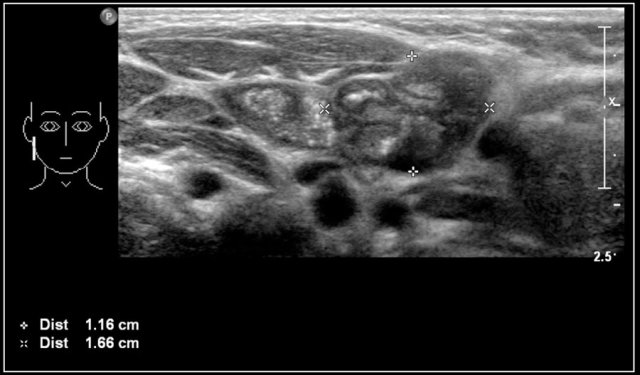

Malignant lymphoma

Malignant lymphoma presents with painless lymphadenopathy.

In Hodgkin lymphoma the cervical nodes are most commonly involved, while in non-Hodgkin lymphoma the nodes of the Waldeyer ring are often involved.

On ultrasound the affected nodes are round, homogeneously hypoechoic and the normal echogenic hilum is absent.

The diagnosis is made by ultrasound-guided biopsy or excision.

PET/CT will demonstrate the extension of the disease.

The images are of a fourteen-year-old boy with a painless swelling in the left neck.

The ultrasound shows several enlarged hypoechoic lymhnodes, that lack an hyper-echoic hilum.

Here another fourteen-year-old boy with a painless swelling in the left neck.

Ultrasound showed several enlarged lymhnodes.